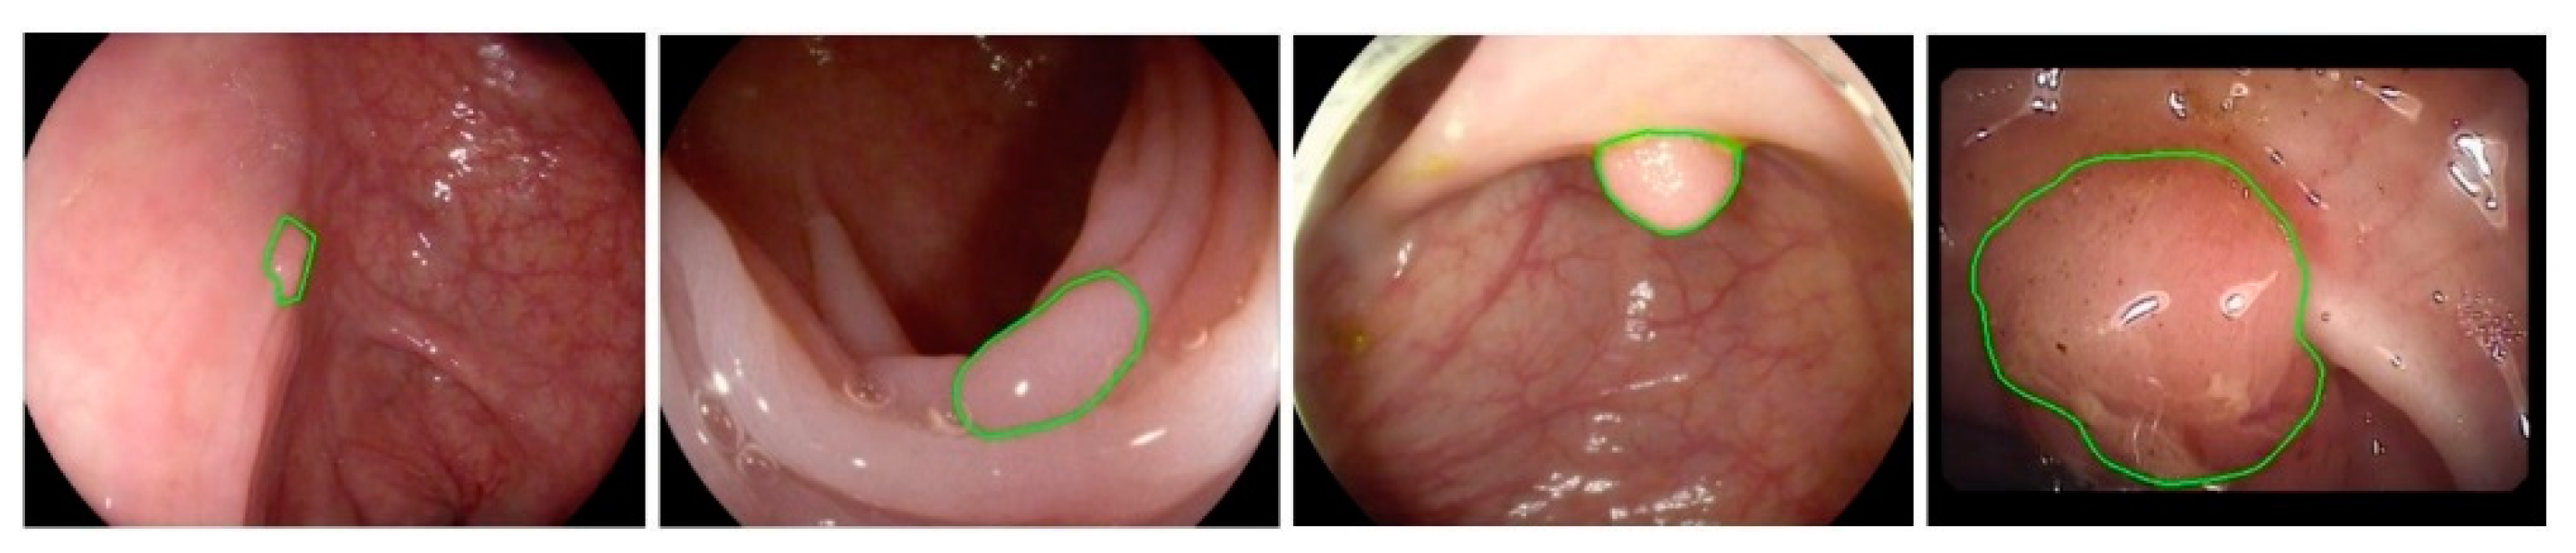

There are various challenges in the automated detection of polyps. As shown in Figure 1 and Figure 2, polyps appear in different sizes, shapes, textures, and color. Their endoscopic appearance can be similar to protruded lesions, flat elevated lesions, and flat lesions. The images even have noisy background with bleeding and endoluminal folds, which suppresses the accuracy of the detection process.

Figure 2.

Images with ground truth polyps (marked in green) from wireless capsule endoscopy (WCE) videos.